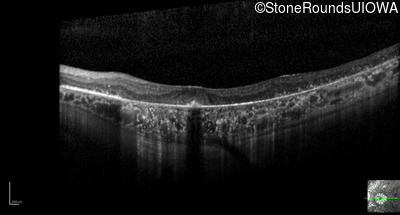

Optical Coherence Tomography - Left - 20/32

Exemplar / OCT Stack